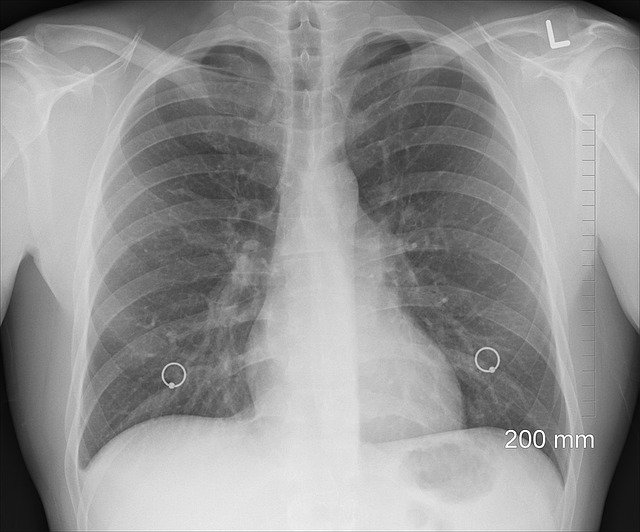

폐암은 초기 증상이 모호한 만큼 정기적인 검진이 가장 강력한 예방법입니다. 특히 40세 이상 흡연 경력이 있는 분들은 저선량 흉부 CT 검사를 통해 폐 건강을 체크하는 것이 매우 효과적입니다.